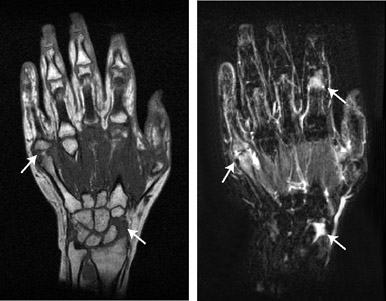

関節症状を訴え医療機関を受診したが、抗CCP抗体も含めて血清学的所見に異常がないため、経過観察されている症例は多く存在する。この症例は,3年前に右第2MCP関節の疼痛を自覚し,近医を受診した。しかし、身体所見,血清学的所見,単純X線写真上では異常を認めなかった。以後、症状が出現するたびに受診を続けていたがやはり、異常所見を認めなかった。

しかし、右第1MCP関節、左第5MCP関節・手関節の疼痛が継続して出現するようになったため、単純X線を撮影したところ,骨びらんを認めた。このため当科に紹介となり,コンパクトMRIの撮像を行った。当科受診時、CRP 0.17mg / dL、MMP-3 37.4ng / mL、RF 3IU / mL、CARF 1.2AU / mL、抗CCP抗体 4.5U / mL未満、抗核抗体 20倍未満と,血清学的には異常所見は認められなかった。しかし、コンパクトMRIを撮像したところ,患者の自覚症状の部位と一致して滑膜炎と骨びらんを認め、また,両手根間関節,左第2PIP関節でも滑膜炎を認めた(図1)。

a:T1強調画像(左手) b:STIR法(左手) |

c:T1強調画像(右手) d:STIR法(右手) |

図1 コンパクトMRI画像によるリウマチ早期診断例

左第5MCP関節,右第1MCP関節で,滑膜炎と骨びらんを認める。

また,両手根間関節,左第2PIP関節でも滑膜炎を認める。

・STIR:3D-STIR-FSE

TR/TEeff/TI = 1000 ms/70 ms/110 ms

Voxel size = 0.8 mm X 0.8 mm X 3.2 mm

Tacq = 6 min 30 sec

・T1WI:3D-GE

TR/TE/FA = 40 ms/5 ms/65 deg

Voxel size = 0.4 mm X 0.8 mm X 1.6 mmm

Tacq = 5 min 30 sec